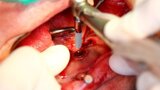

Implantacja z wykorzystaniem szablonu nawigacyjnego 3D